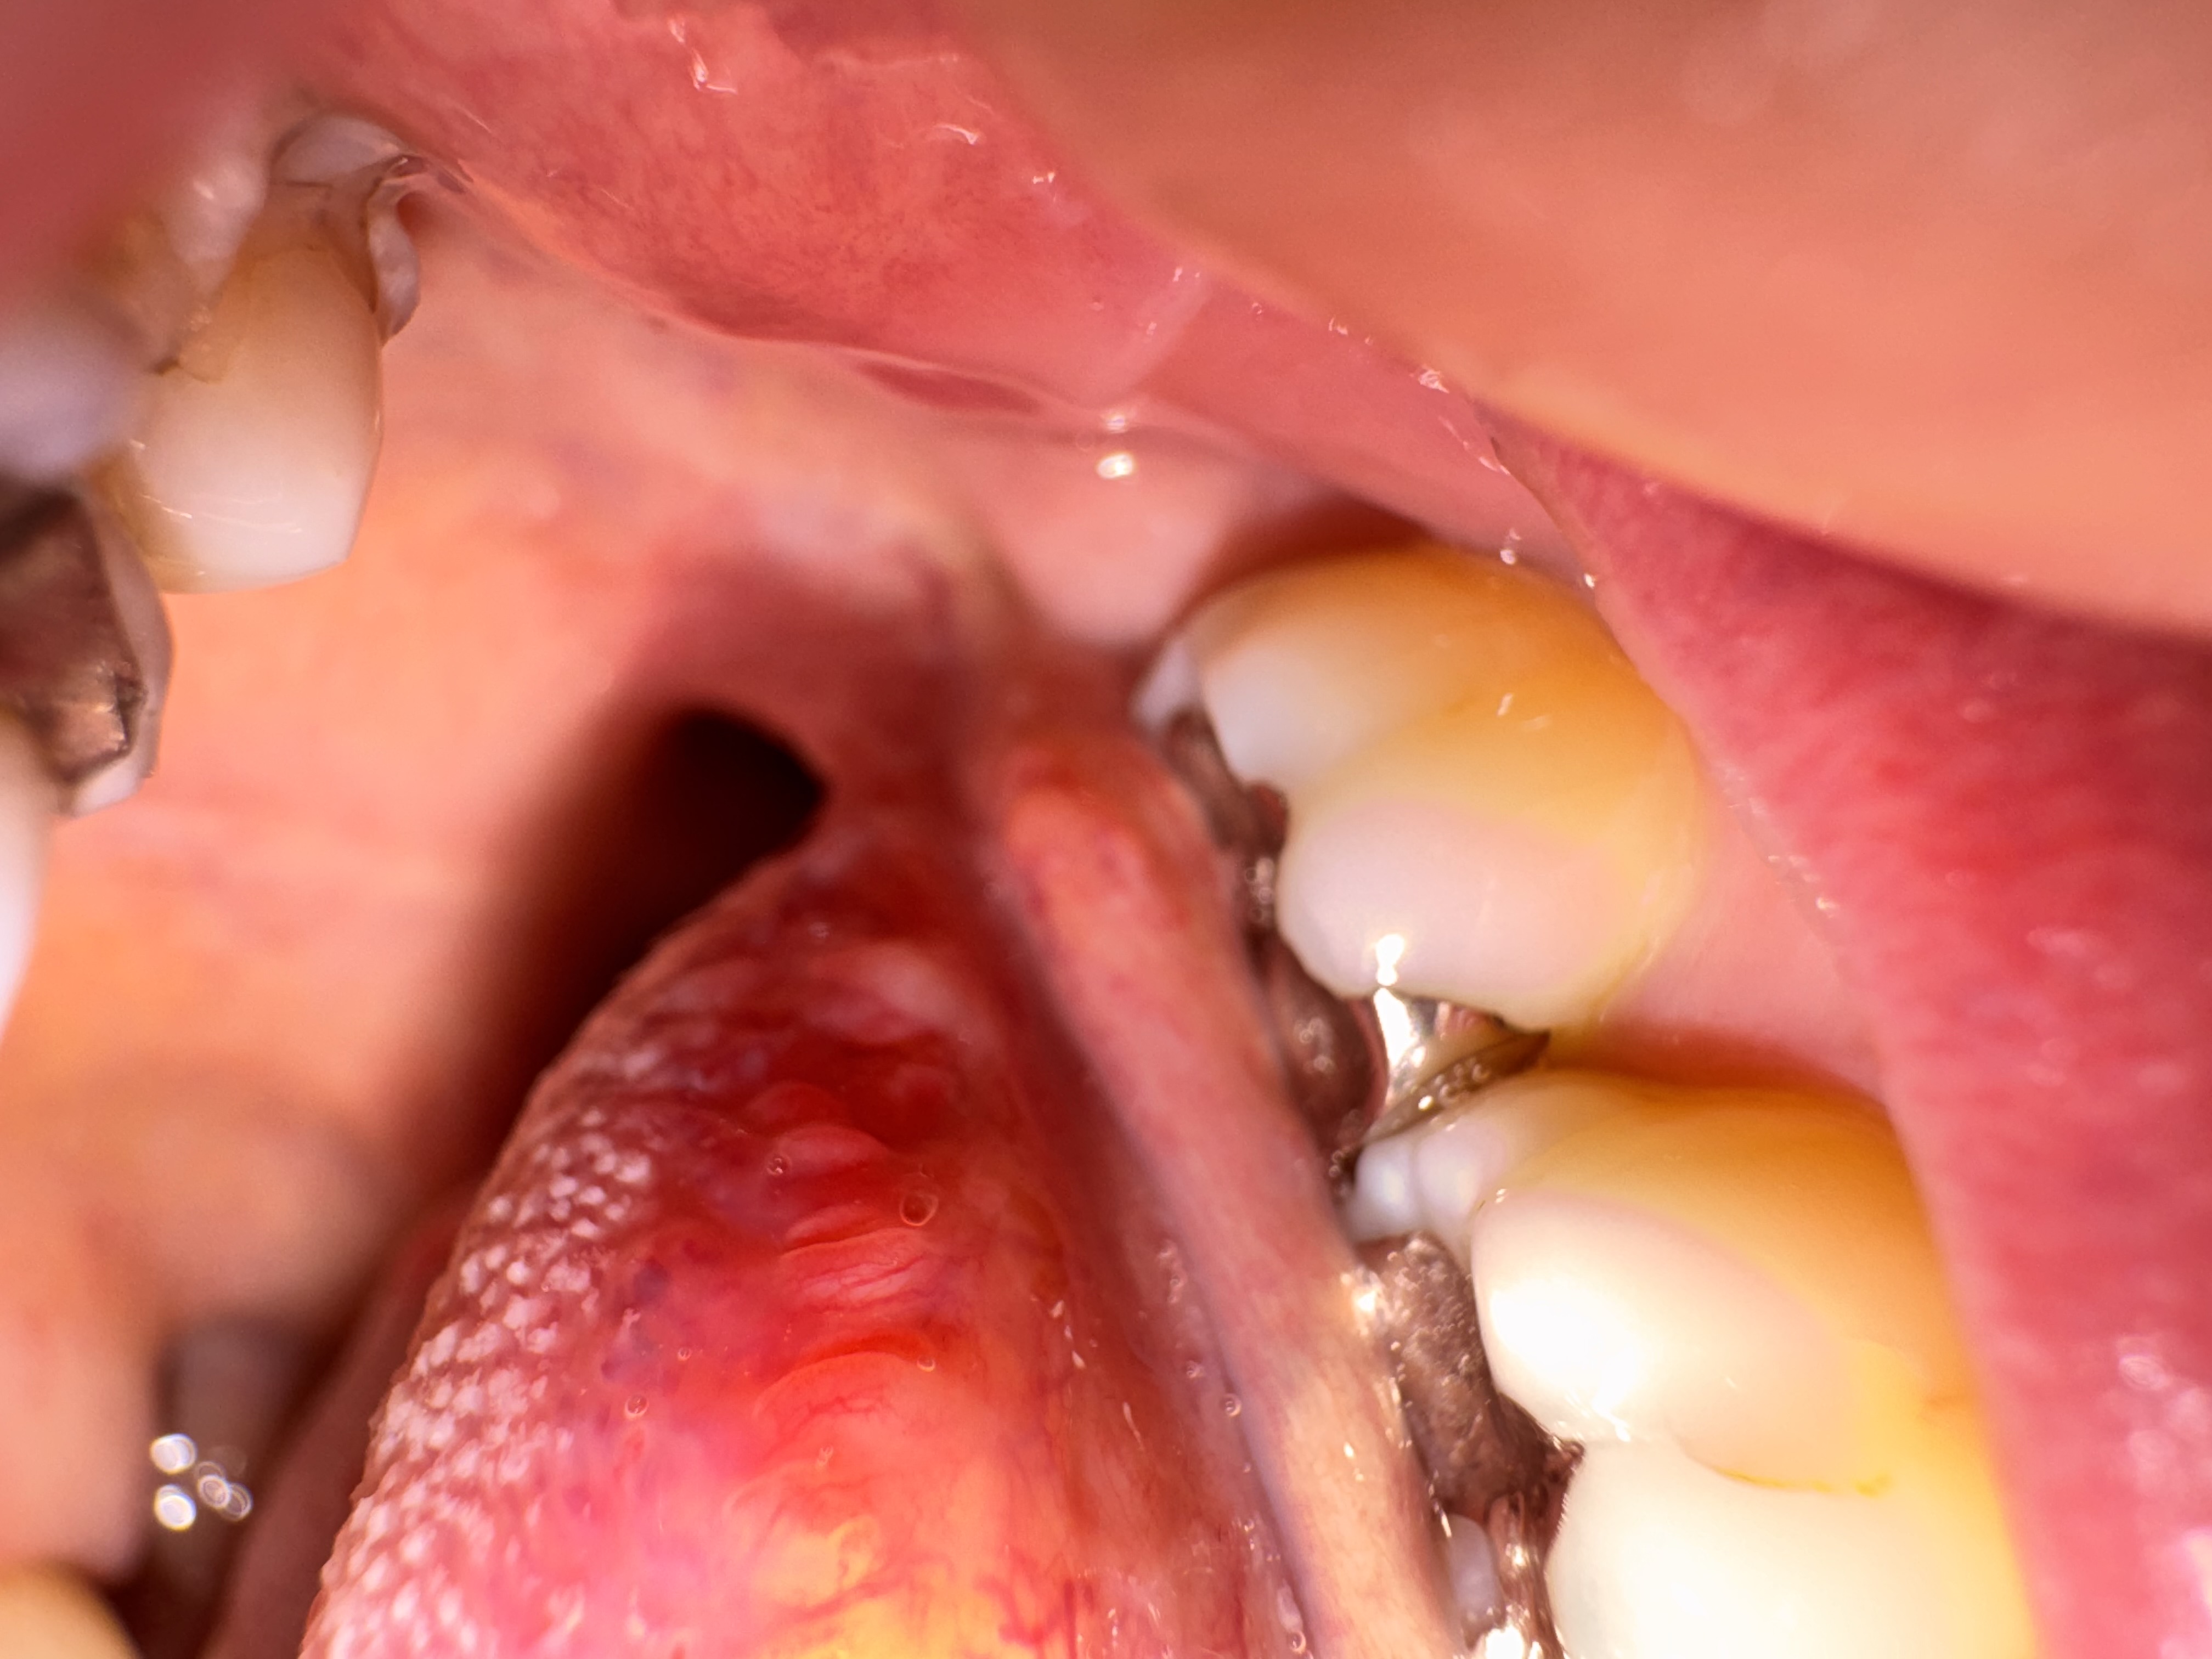

舌の側面に透明な出来物ができました。